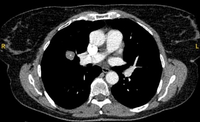

Tomografia computadorizada (TC) mostrando um pequeno nódulo no lobo superior esquerdo com margens lisas, posteriormente considerado uma metástase colorretal solitária na ressecção

Do acervo de Dr. George Tsaknis, MD, PhD, FRCP (Londres), MRQA, MAcadMEd, PGCert; usado com permissão